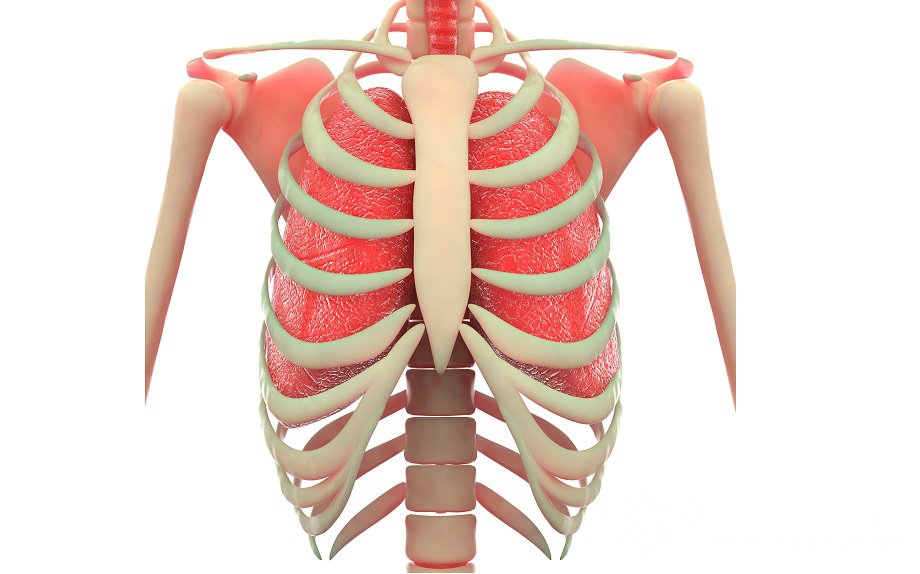

Грудина – непарная удлиненная кость со слегка выпуклой передней частью и вогнутой задней поверхностью. Строение грудины Г...

Читать далее